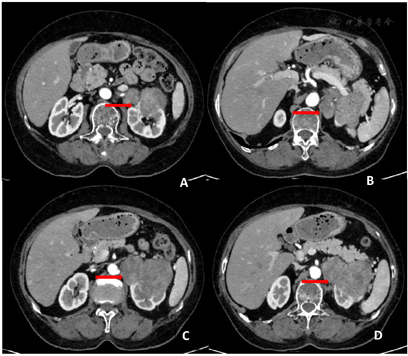

由于该团块与左侧肾脏分界不清晰,为了了解其与肾脏的关系,进一步行腹部增强CT检查。CT显示左侧肾上腺-左肾区见以不规则形软组织肿块影伴少许钙化,截面约8.0 cm×5.5 cm,增强扫描显示该肿块出现不均匀强化,周围组织呈受压推移改变,考虑肿瘤性病变,肾上腺来源可能性大(图2)。

ACC的影像学诊断主要依靠超声、CT及MRI等检查,特别是无内分泌症状的非功能性肿瘤更需要影像学检查明确诊断。超声检查是首选初筛检查,具有无创和可重复的特点,可大致了解肿瘤一般情况、边界、内部及周边血流情况。ACC的超声典型表现为肾上腺区较大低回声占位性病灶,通常直径大于5 cm,内部回声不均匀,边界不清,形态不定,可呈圆形、椭圆形或分叶状,彩色多普勒超声示肿块内部多可探及血流信号,少数周边可见血流信号。肾上腺皮质恶性肿瘤超声声像图表现主要取决于肿瘤的大小,中等大小(3~5 cm)的皮质恶性肿瘤特征性地固定于肾上腺部位,边界清晰,偶可见包膜,内部回声均匀或不均匀[9];大于5 cm的皮质恶性肿瘤可与肝或脾紧密相贴,内部因出血坏死形成的不规则高回声团或无回声,部分病例可见强回声钙化,当较大肿瘤显示分叶状,内见"瘢痕"征,即放射状回声,则恶性可能性变大。疑为ACC的患者还应行腹膜后及腹腔淋巴结扫查,有时可见到肿大淋巴结,部分患者合并有下腔静脉及肾静脉癌栓,病灶可见出血及坏死区,少数可有钙化,癌症容易侵犯肾上腺静脉、下腔静脉,可发生肝,脑,骨转移。CT对于鉴别肿瘤良恶性、确定肿瘤分期及手术方式有重要作用。皮质癌的CT特征性表现为轮廓不规则,密度不均,假包膜形成,中央区沙粒样钙化,内部出血坏死,增强扫描时动脉期不均匀强化,延迟期渐进式持续强化[3]。Xiao等[10]报道CT对于诊断ACC敏感性高达98%,误诊率及漏诊率小于10%。同时CT对于确定肿瘤有无外生性生长,是否淋巴结转移及周围脏器浸润情况有重要意义。